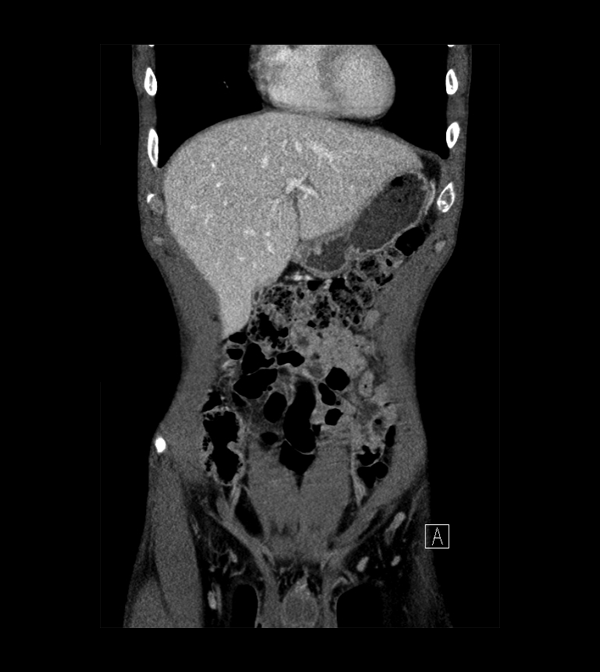

Body

Covers abdominal CT anatomy.